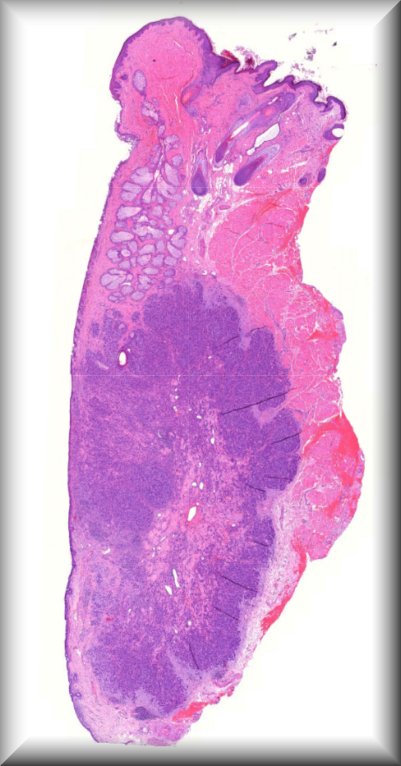

Hind M. Alkatan (Guest): A 10-month-old boy presented with a painless scrotal mass.External examination demonstrated left scrotal non-tender hard mass measuring 4x3 cm in size, with negative transillumination test. Ultrasonography of left scrotum showed a well-circumscribed, oval shaped mass with mixed echogenicity, The mass contained both cystic and solid component, with no clear visualization of the left testicle.The patient underwent left scrotal exploration with high inguinal orchidectomy |